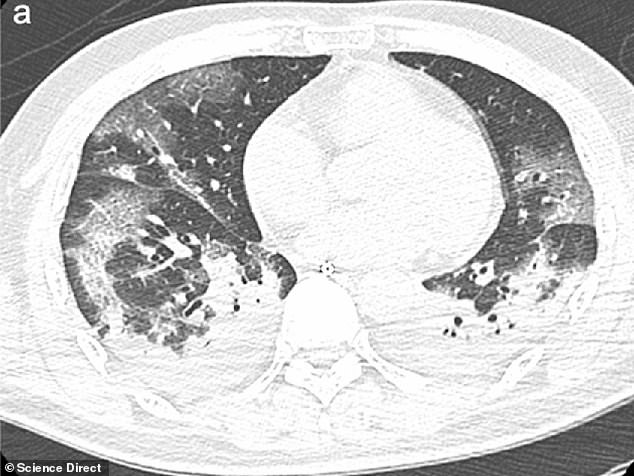

Το ίδιο συμβαίνει και στη μαγνητική τομογραφία στους πνεύμονες όπου στη μια είναι καθαροί και στην άλλη έχουν γεμίσει πυον, νερό ή αίμα.

Τη δεύτερη σάρωση οι μαλακοί ιστοί των πνευμόνων φαίνονται εξαιρετικά διογκωμένοι.